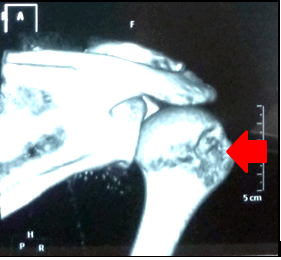

Пример дефицита кости гленоида и головки плечевой кости при множественных вывихах плечевого сустава

Компьютерная томография (КТ) позволяет четко выявить гипоплазию суставного отростка лопатки, его аномальное положение в пространстве. С помощью КТ оценивается наличие и степень дефицита костной ткани гленоида и выраженность повреждения Хилл-Сакса головки плечевой кости. КТ в режиме 3D (трехмерной реконструкции) наглядно демонстрирует повреждение костных структур гленоида лопатки и головки плечевой кости. Основываясь на данных компьютерной томографии, вычисляется степень дефицита гленоида и степень поврежения типа Хилл-Сакса.

Рисунок: Сравнительная характеристика суставных поверхностей лопатки правого и левого плеча в режиме трехмерной реконструкции, наглядно демонстрирующая наличие костного дефицита лопатки.